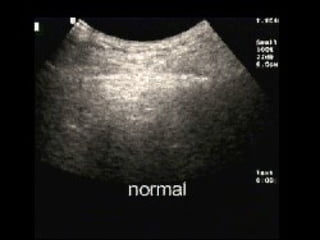

Absent lung sliding

Absent lung sliding Exaggeratedhorizontal artifacts Loss of comet-tail artifacts Broadening of the pleural line to a band The key sonographic signs of Pneumothorax